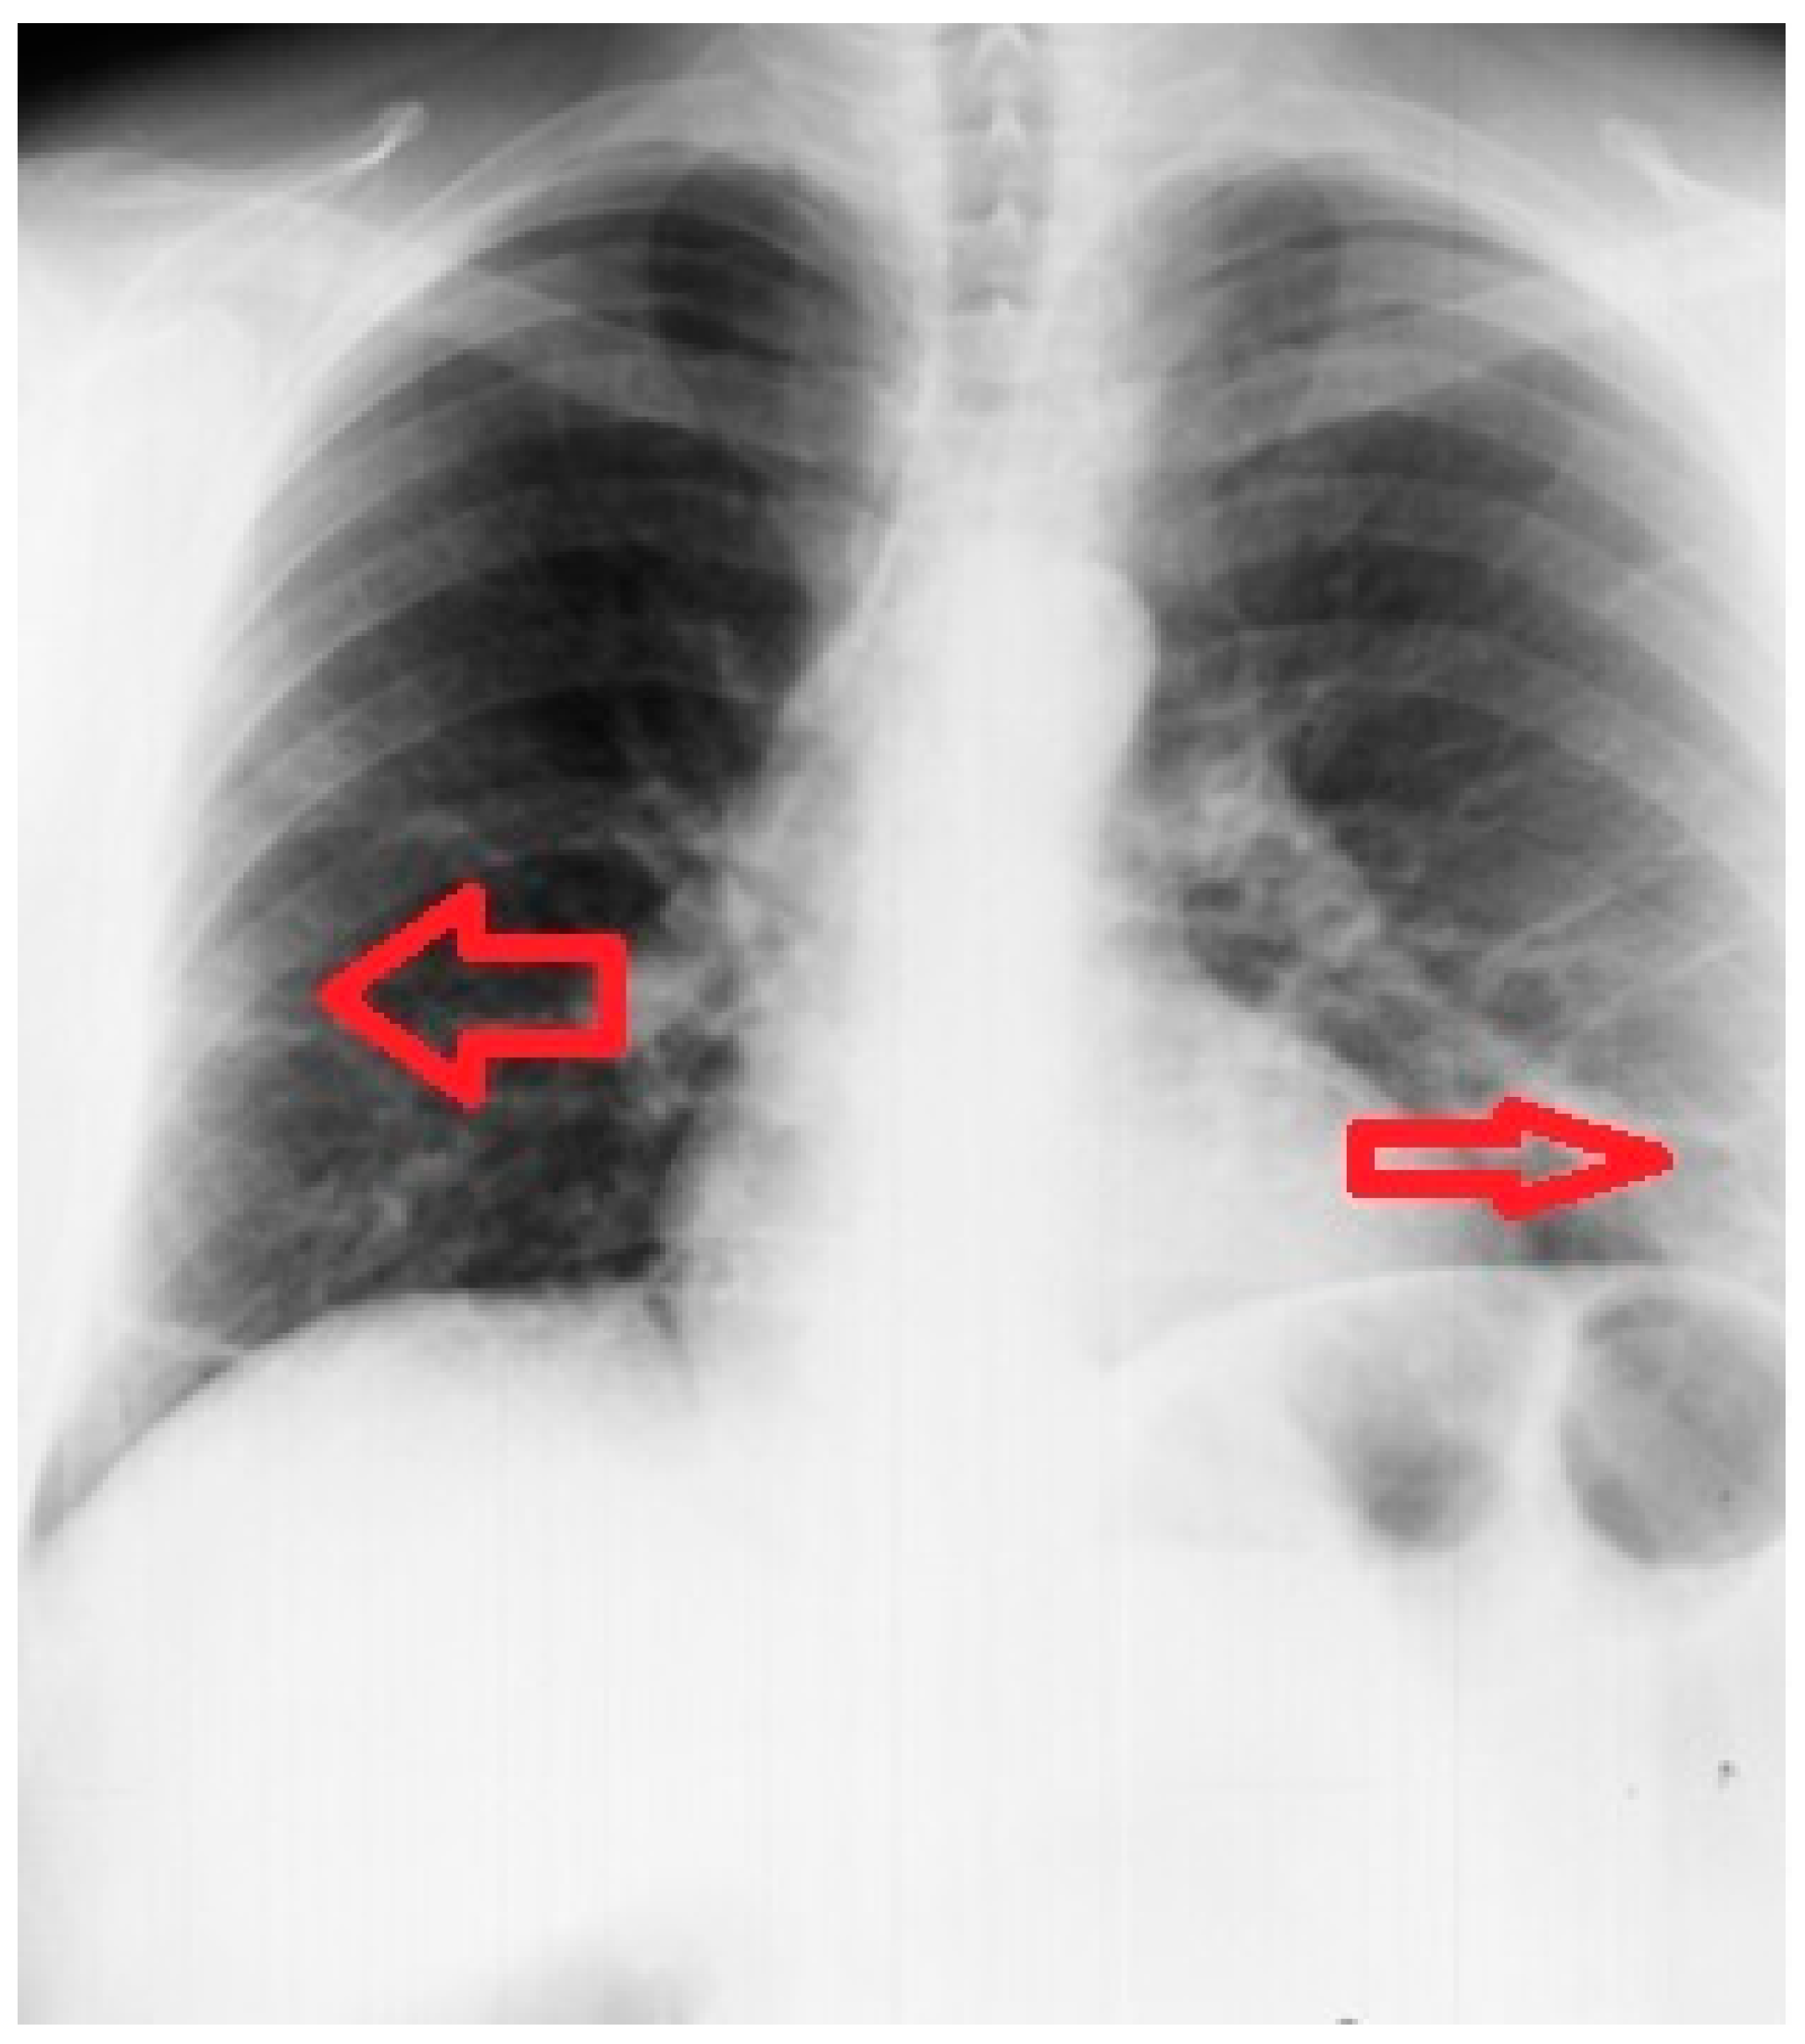

2. Case Report